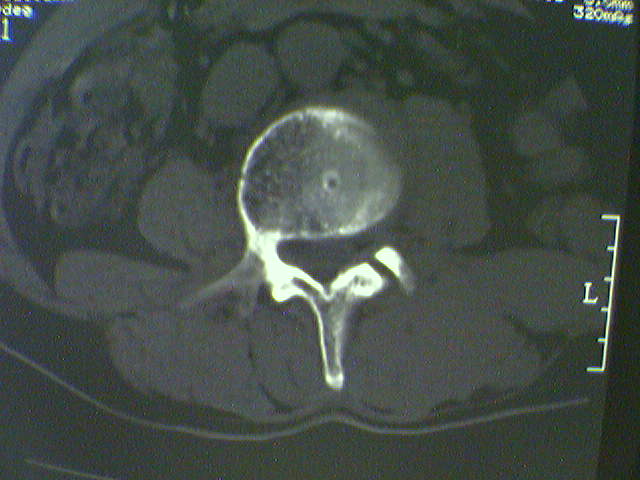

标题: CT15569:男,45岁.腰痛多年,平片腰椎明显侧弯, [打印本页]

标题: CT15569:男,45岁.腰痛多年,平片腰椎明显侧弯,

退行性变

侧弯,退变.

考虑退变。